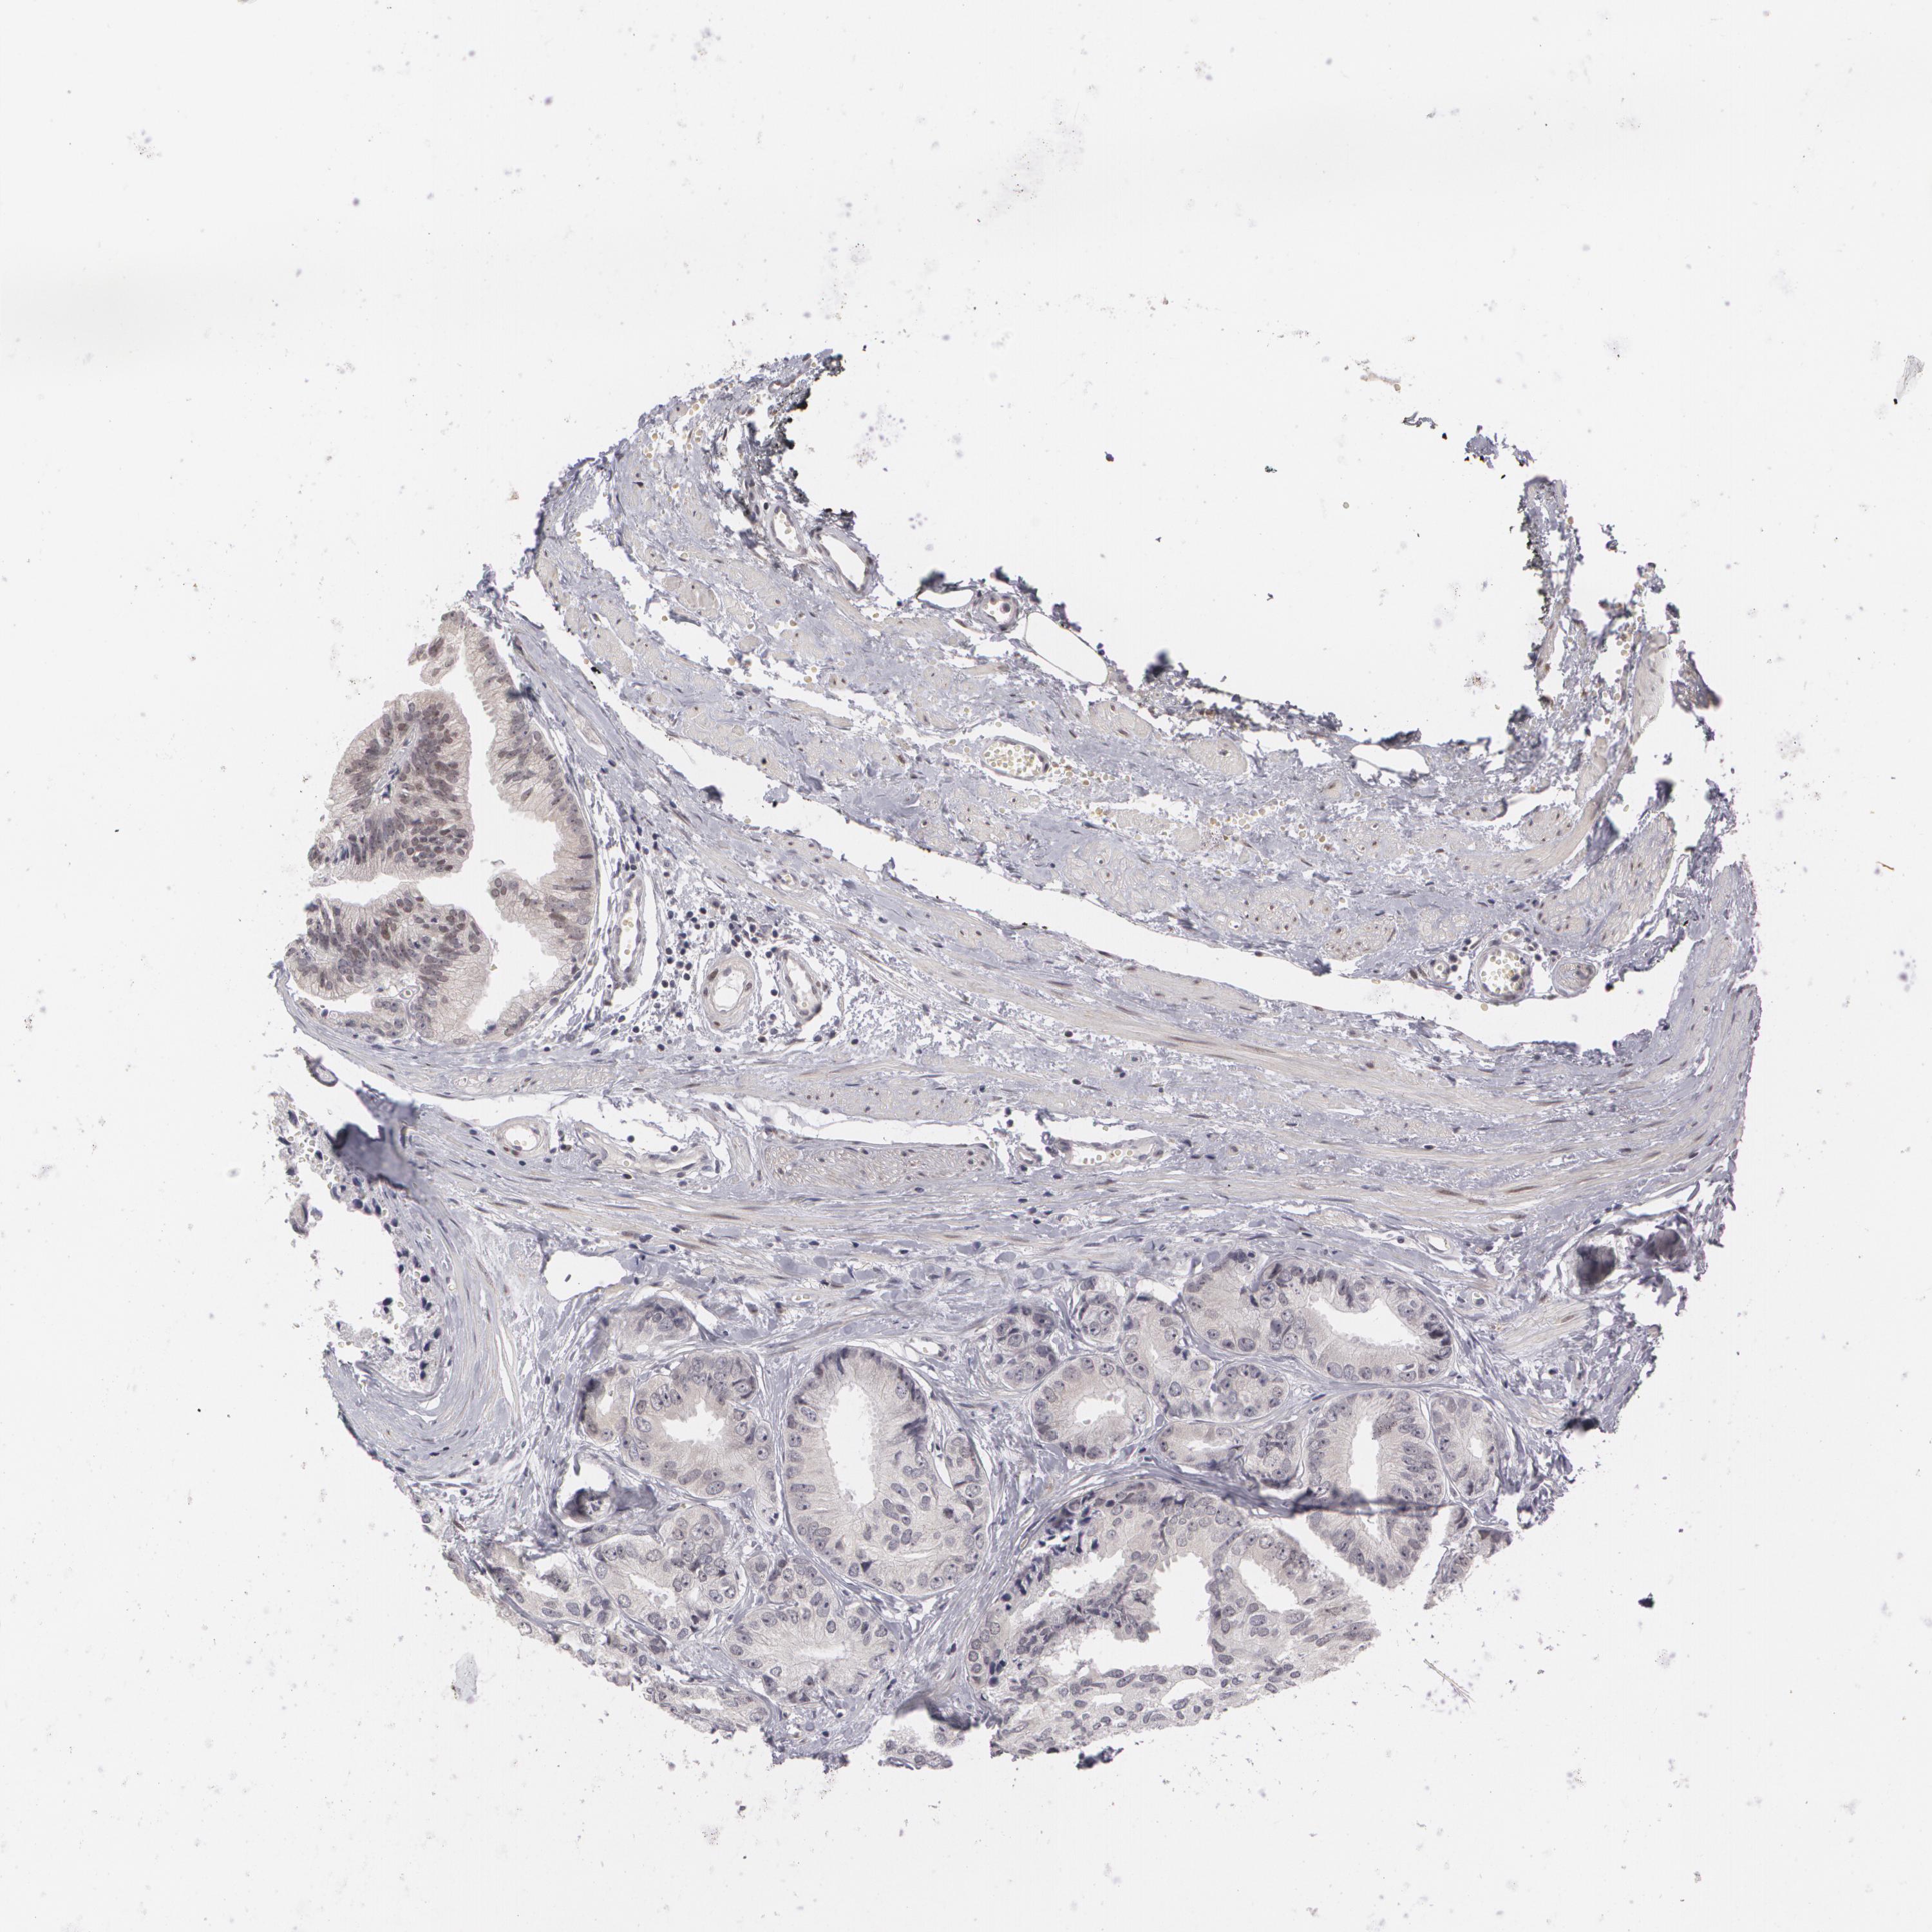

PROSTATE CANCER - Protein expressioni

A mouse-over function shows sample information and annotation data. Click on an image to view it in a full screen mode. Samples can be filtered based on level of antibody staining by selecting one or several of the following categories: high, medium, low and not detected. The assay and annotation is described here.

Antibody stainingi

Antibody staining in the annotated cell types in the current human tissue is reported as not detected, low, medium, or high, based on conventional immunohistochemistry profiling in selected tissues. This score is based on the combination of the staining intensity and fraction of stained cells.

Each image is clickable and will lead to virtual microscopy that enables deeper exploration of all samples and also displays staining intensity scores, fraction scores and subcellular localization as well as patient and tissue information for each sample.

Antibody HPA001499

Adenocarcinoma, Medium grade

Adenocarcinoma, High grade

Adenocarcinoma, Low grade